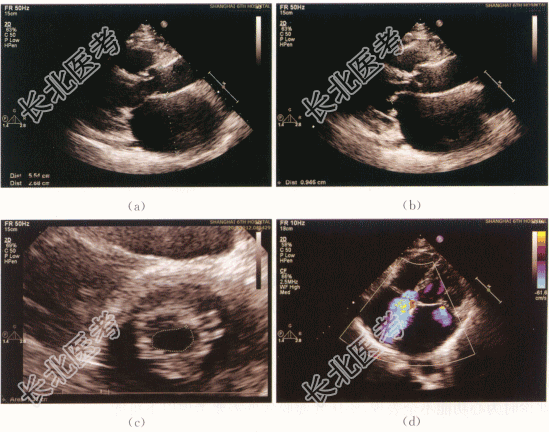

患者,男性,59岁,因“间断心慌、气促发作3年”就诊。患者于3年前突发心慌、气促,与活动相关,多发生在重体力劳动时,伴有夜间阵发性呼吸困难,夜间不能平卧,无双下肢水肿,无胸闷、胸痛,无头晕、黑矇,无晕厥发生。

患者血压110mmHg/67mmHg,气平,无贫血貌,双肺听诊呼吸音清,肺底未及啰音。心浊音界大致正常,心率52次/min,律不齐,P2=A2,二尖瓣听诊区可及2/6级舒张期杂音。腹壁柔软,无腹部压痛。双下肢无水肿。

RBC、Hb升高,ESR正常,尿蛋白升高,ANP升高。心电图:心房颤动,ST段水平压低(V5,V6)。

二、影像资料